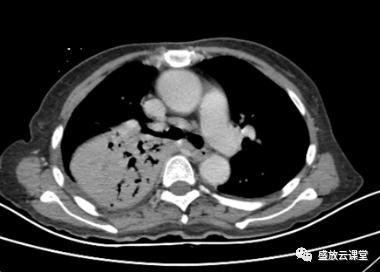

【病例】肺淋巴瘤(MALT)一例CT影像

【病例】肺淋巴瘤(MALT)一例CT影像-5 【病例】肺淋巴瘤(MALT)一例CT影像-6

【病例】肺淋巴瘤(MALT)一例CT影像-3